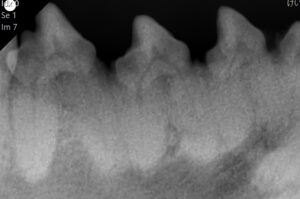

📷 歯科レントゲン写真(アンキローシス)

歯科用レントゲン検査を行ったところ、歯と顎の骨が癒着してしまう「アンキローシス」が全体的に進行していることが分かりました。レントゲン上で歯根膜が消失しているのがわかります。